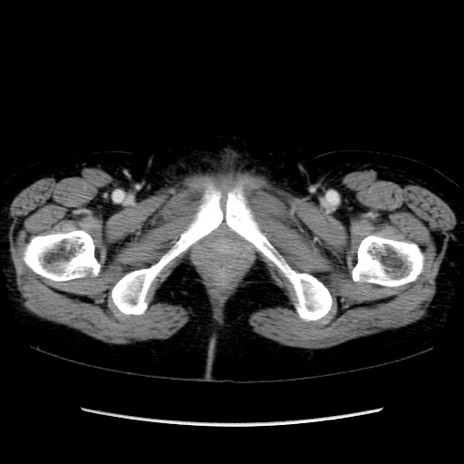

症例32(横断像)

【症例】40歳代 女性

【主訴】上腹部痛、嘔気・嘔吐

【現病歴】約9時間前頃から急に上腹部痛、嘔気、嘔吐が出現。改善しないため救急要請。

【既往歴】子宮頚癌(広汎子宮全摘術、放射線療法)、腸閉塞